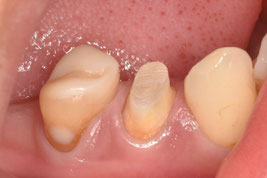

軸面の健全歯質を大幅に残したうえで、オーバーレイの形態で修復しました。インジェクションモールディング法を応用しております。直接修復なので、海外からの来院であっても、短期滞在で対応可能です。

右下4番の治療を希望されて、1年ぶりに来院してくれました。問題なく良好に経過しているとのことで、とても安心しました。

1回法による根管治療で進めました。1回法だと3時間くらい口を開けっ放しになるので、患者さんは辛いと思います。ご協力いただき大変恐縮です。

インジェクションモールディング法を用いて、ダイレクトクラウンにて完了させました。ファイバーコアによる支台築造と同時にダイレクトクラウンを成形するため、歯根・築造体・クラウンとが一体化したモノブロック構造で強度を担保できます。ファイバーコアからダイレクトクラウンまで一気に進めて、だいたい2時間の施術時間です。施術中にドクターが離れることができないのですが、圧倒的な時間短縮です。